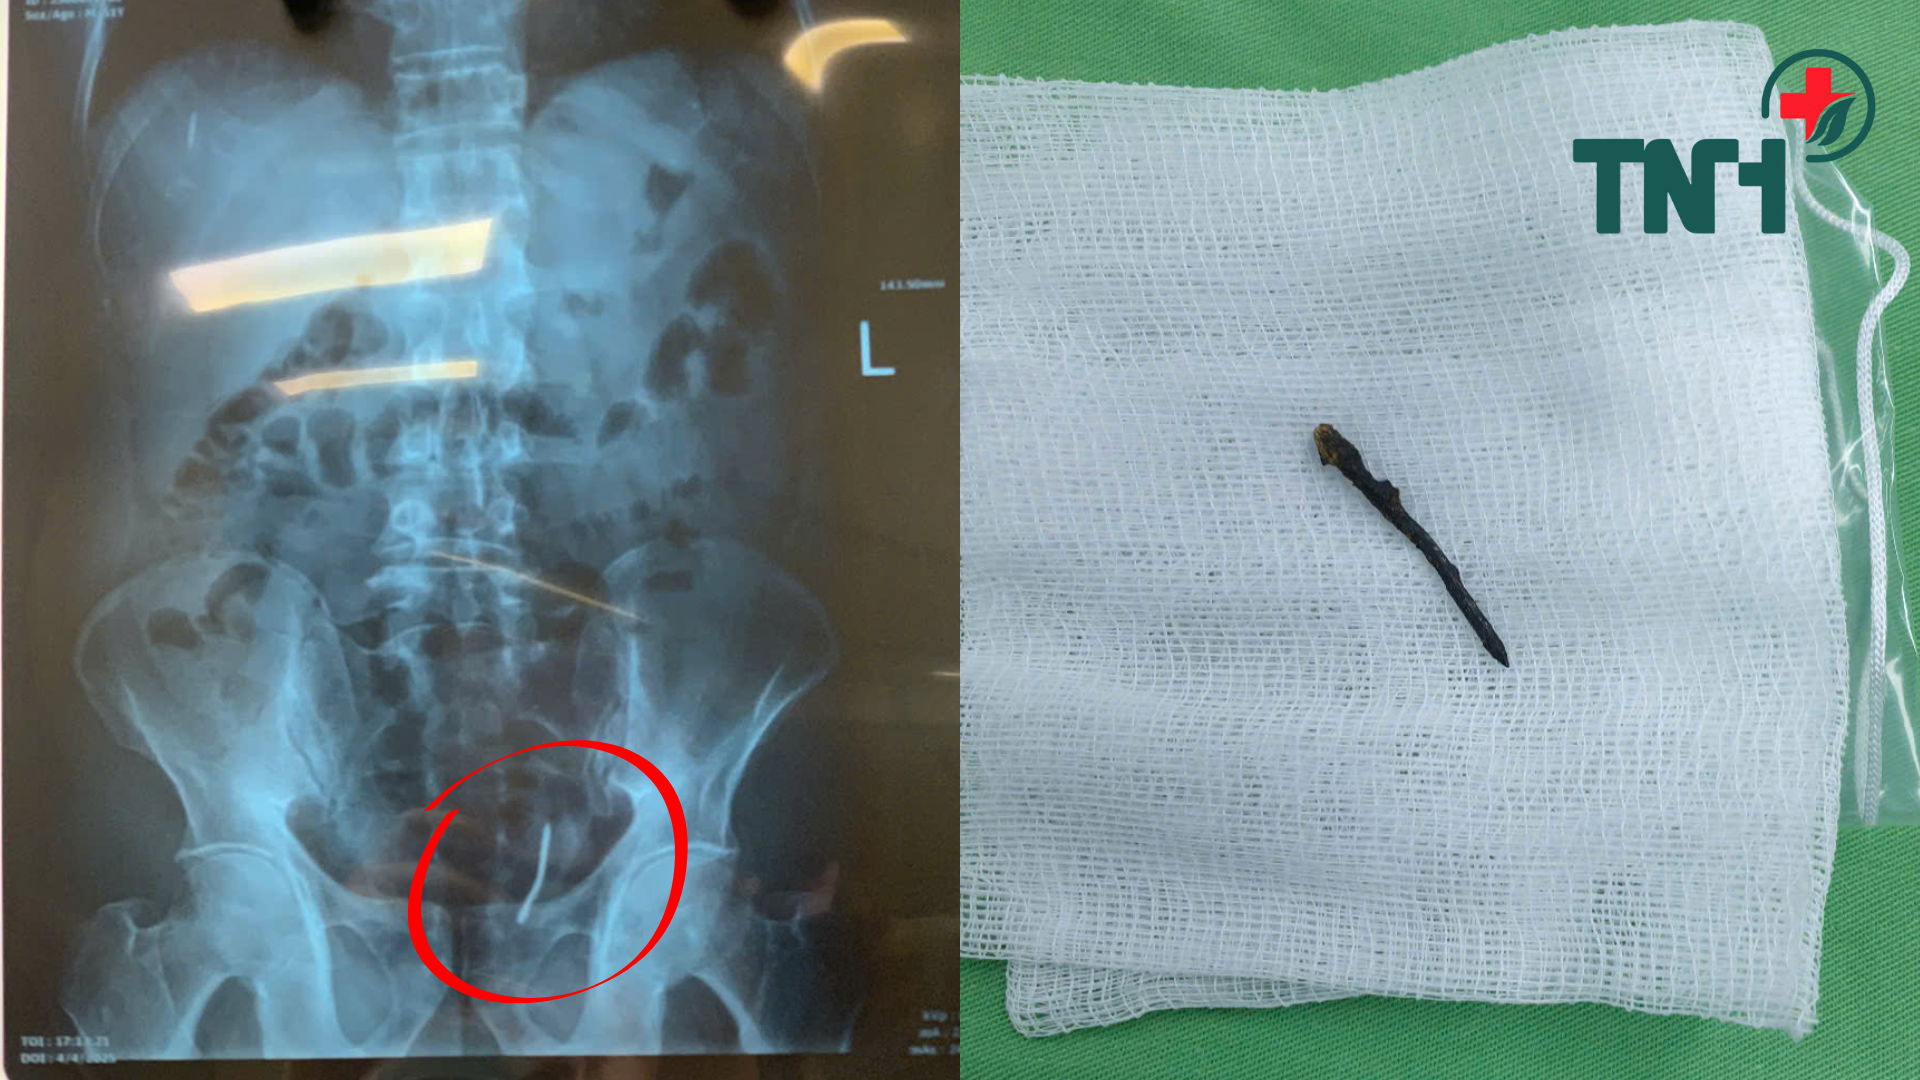

Bệnh nhân vào viện trong tình trạng đau bụng vùng hạ vị, siêu âm vùng tiểu khung phía sau tiền liệt tuyến có một khối cấu trúc dạng dịch, kích thước 28x20mm. Chụp X-quang kỹ thuật số và CT thấy có dị vật là một chiếc đinh có kích thước ~ 3,7cm nằm cạnh bên trái thành trực tràng.

Ca phẫu thuật đã diễn ra thành công tốt đẹp, các bác sĩ đã lấy được dị vật là chiếc đinh sắt hoen gỉ, nằm dưới phúc mạc, sát thành trực tràng. Sau phẫu thuật, bệnh nhân được theo dõi chăm sóc chu đáo và ra viện sau 1 tuần điều trị. Phẫu thuật đã thành công ngoài mong đợi, bảo tồn được thành trực tràng. Bệnh nhân không phải làm hậu môn nhân tạo.